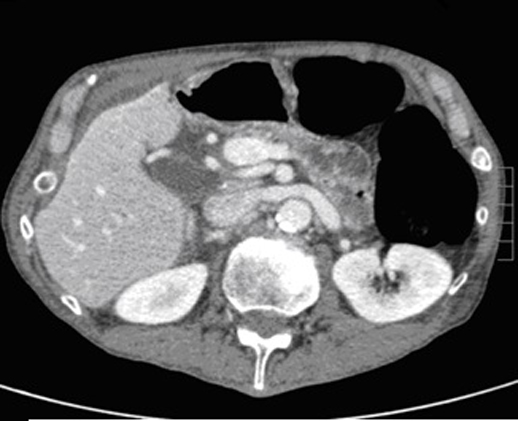

Image TDM :

Image radiologiquer TDM de syndrome de Mirizzi est la

presence de calcul et une epaisissement de la paroi vesicule

biliaire rehaussement hyperdense par le contrast . La dilatation de voie

biliaire pricipale ( canal hepatique commune ) peut se

en voyait . .

Image une calcul a

infundubulum du vesicule biliaire ( fleche

rouge ) avec epaississement de la paroi

vesiculaire : Image TDM en coupe axiale

avec contrast intraveineuse |